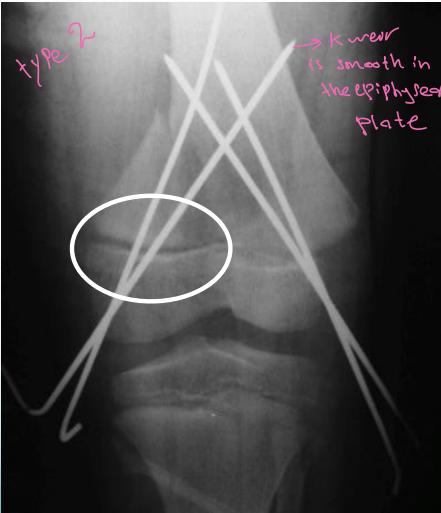

- Unstable: K-wire / screws with cast

Intra-articular (Type III / IV)

- Anatomical reduction and internal fixation

Case Example: 12-year-old male, Salter-Harris Type II